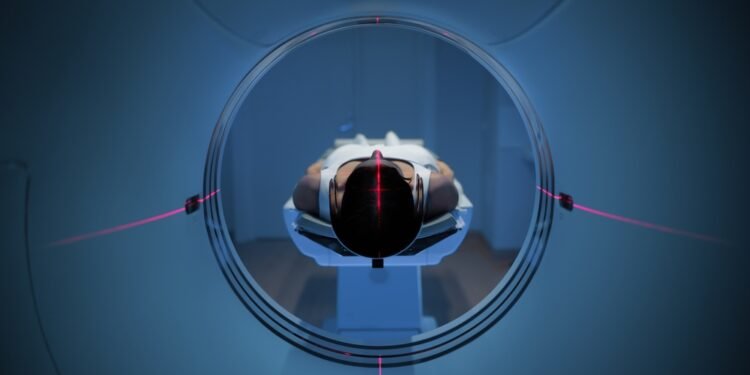

Magnetinio rezonanso tomografija, dar vadinama MRT, yra neinvazinis medicininės diagnostikos metodas, leidžiantis gauti itin detalius beveik visų žmogaus kūno vidinių struktūrų vaizdus. Šiuo tyrimu galima tiksliai įvertinti vidaus organus, kaulus, raumenis, kraujagysles ir kitus audinius. MRT įrenginiai vaizdus formuoja naudodami stiprų magnetinį lauką ir radijo bangas. Skirtingai nei rentgeno tyrimuose, šio proceso metu nenaudojama jonizuojančioji spinduliuotė. Gauti vaizdai suteikia gydytojui svarbios informacijos, reikalingos ligos diagnostikai ir tinkamo gydymo plano sudarymui.

MRT aparatas yra didelis cilindro formos įrenginys, sukuriantis stiprų magnetinį lauką aplink pacientą ir siunčiantis radijo bangų impulsus. Kai kurie aparatai yra siauro tunelio tipo, kiti – atviresnės konstrukcijos.

Tyrimas atliekamas specialioje vamzdžio formos erdvėje, atviroje iš abiejų galų. Norint gauti kokybiškus vaizdus, būtina viso tyrimo metu išlikti visiškai nejudriam. Aparatas skleidžia stiprų triukšmą, todėl pacientui suteikiami ausų kamštukai.

Jūs atsigulsite ant specialaus stalo, kuris lėtai įstumiamas į didelę apvalią MRT aparato angą. Siekiant išvengti judesių, gali būti naudojamos pagalvės ar dirželiai.